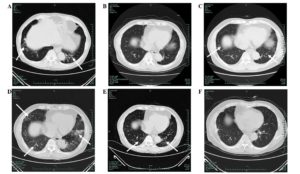

Для дифференциальной диагностики пневмонита и пневмонии полезны визуализирующие методы. При пневмонии поражается небольшая часть легочной ткани, тогда как пневмонит затрагивает все доли легких. Назначаются такие исследования:

- Рентгенография органов грудной клетки

- Компьютерная томография

Пневмонит на КТ диагностируется по таким признакам:

Также могут определяться расширения бронхов – бронхоэктазы, узелки в ткани легких. Изменения симметричны, что является еще одним отличием от пневмонии.

Отличие пневмонита от воспаления лёгких (пневмонии) чётко видно на рентгеновских снимках. В первом случае лёгочный рисунок усилен, наблюдаются затемнения в нижней части лёгких, во втором — очаги затемнения имеют неровные контуры в различных участках лёгких.